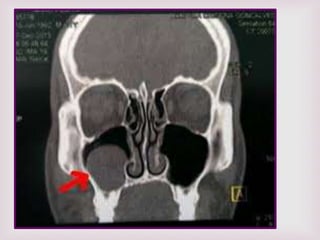

EXÁMENES RADIOGRÁFICO

RX SENOS PARANASALES

De poca ayuda en el dx de pólipos

nasales altos falsos positivos y falsos

negativos.

TUMOGRAFIA COMPUTADA TC

Para confirmar localización y

extensión de la lesión. De gran

utilidad permite planear tipo de

cirugía y evitar complicaciones .

RMN.

Se usa para diferenciar pólipos de:

-Tumores

-Mucoceles

-Infección fúngica